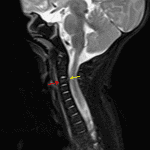

Age: 2 months

Sex: Male

Indication: Trauma, no fracture on CT

Findings

- STIR signal hyperintensity in the anterior aspect of the C3 vertebral body without associated height loss or malalignment

- Focal discontinuity of the posterior longitudinal ligament at the level of C3

- Thin anterior epidural collection at the level of C3 without significant associated narrowing of the spinal canal

- T2/STIR signal hyperintensity in the right greater than left C2-C3 facet joints

- Prevertebral soft tissue thickening extending from the craniocervical junction to the level of C4 with T2/STIR signal hyperintensity and areas of T1 signal hyperintensity

- T2/STIR signal hyperintensity in the posterior paraspinal soft tissues, most notably at the level of C2-C3

Diagnosis

- Cervical spine fracture and ligamentous injury

STIR signal hyperintensity in the anterior aspect of the C3 vertebral body concerning for acute fracture. No associated height loss or malalignment.

Thin ventral epidural hematoma at this level without significant associated spinal canal stenosis or cord signal abnormality.

Focal disruption of the posterior longitudinal ligament at the level of C3. Fluid in the right greater than left facet joints at C2-C3 raises concern for facet capsular injury. Prevertebral edema/hematoma extending from the craniocervical junction to the level of C4.